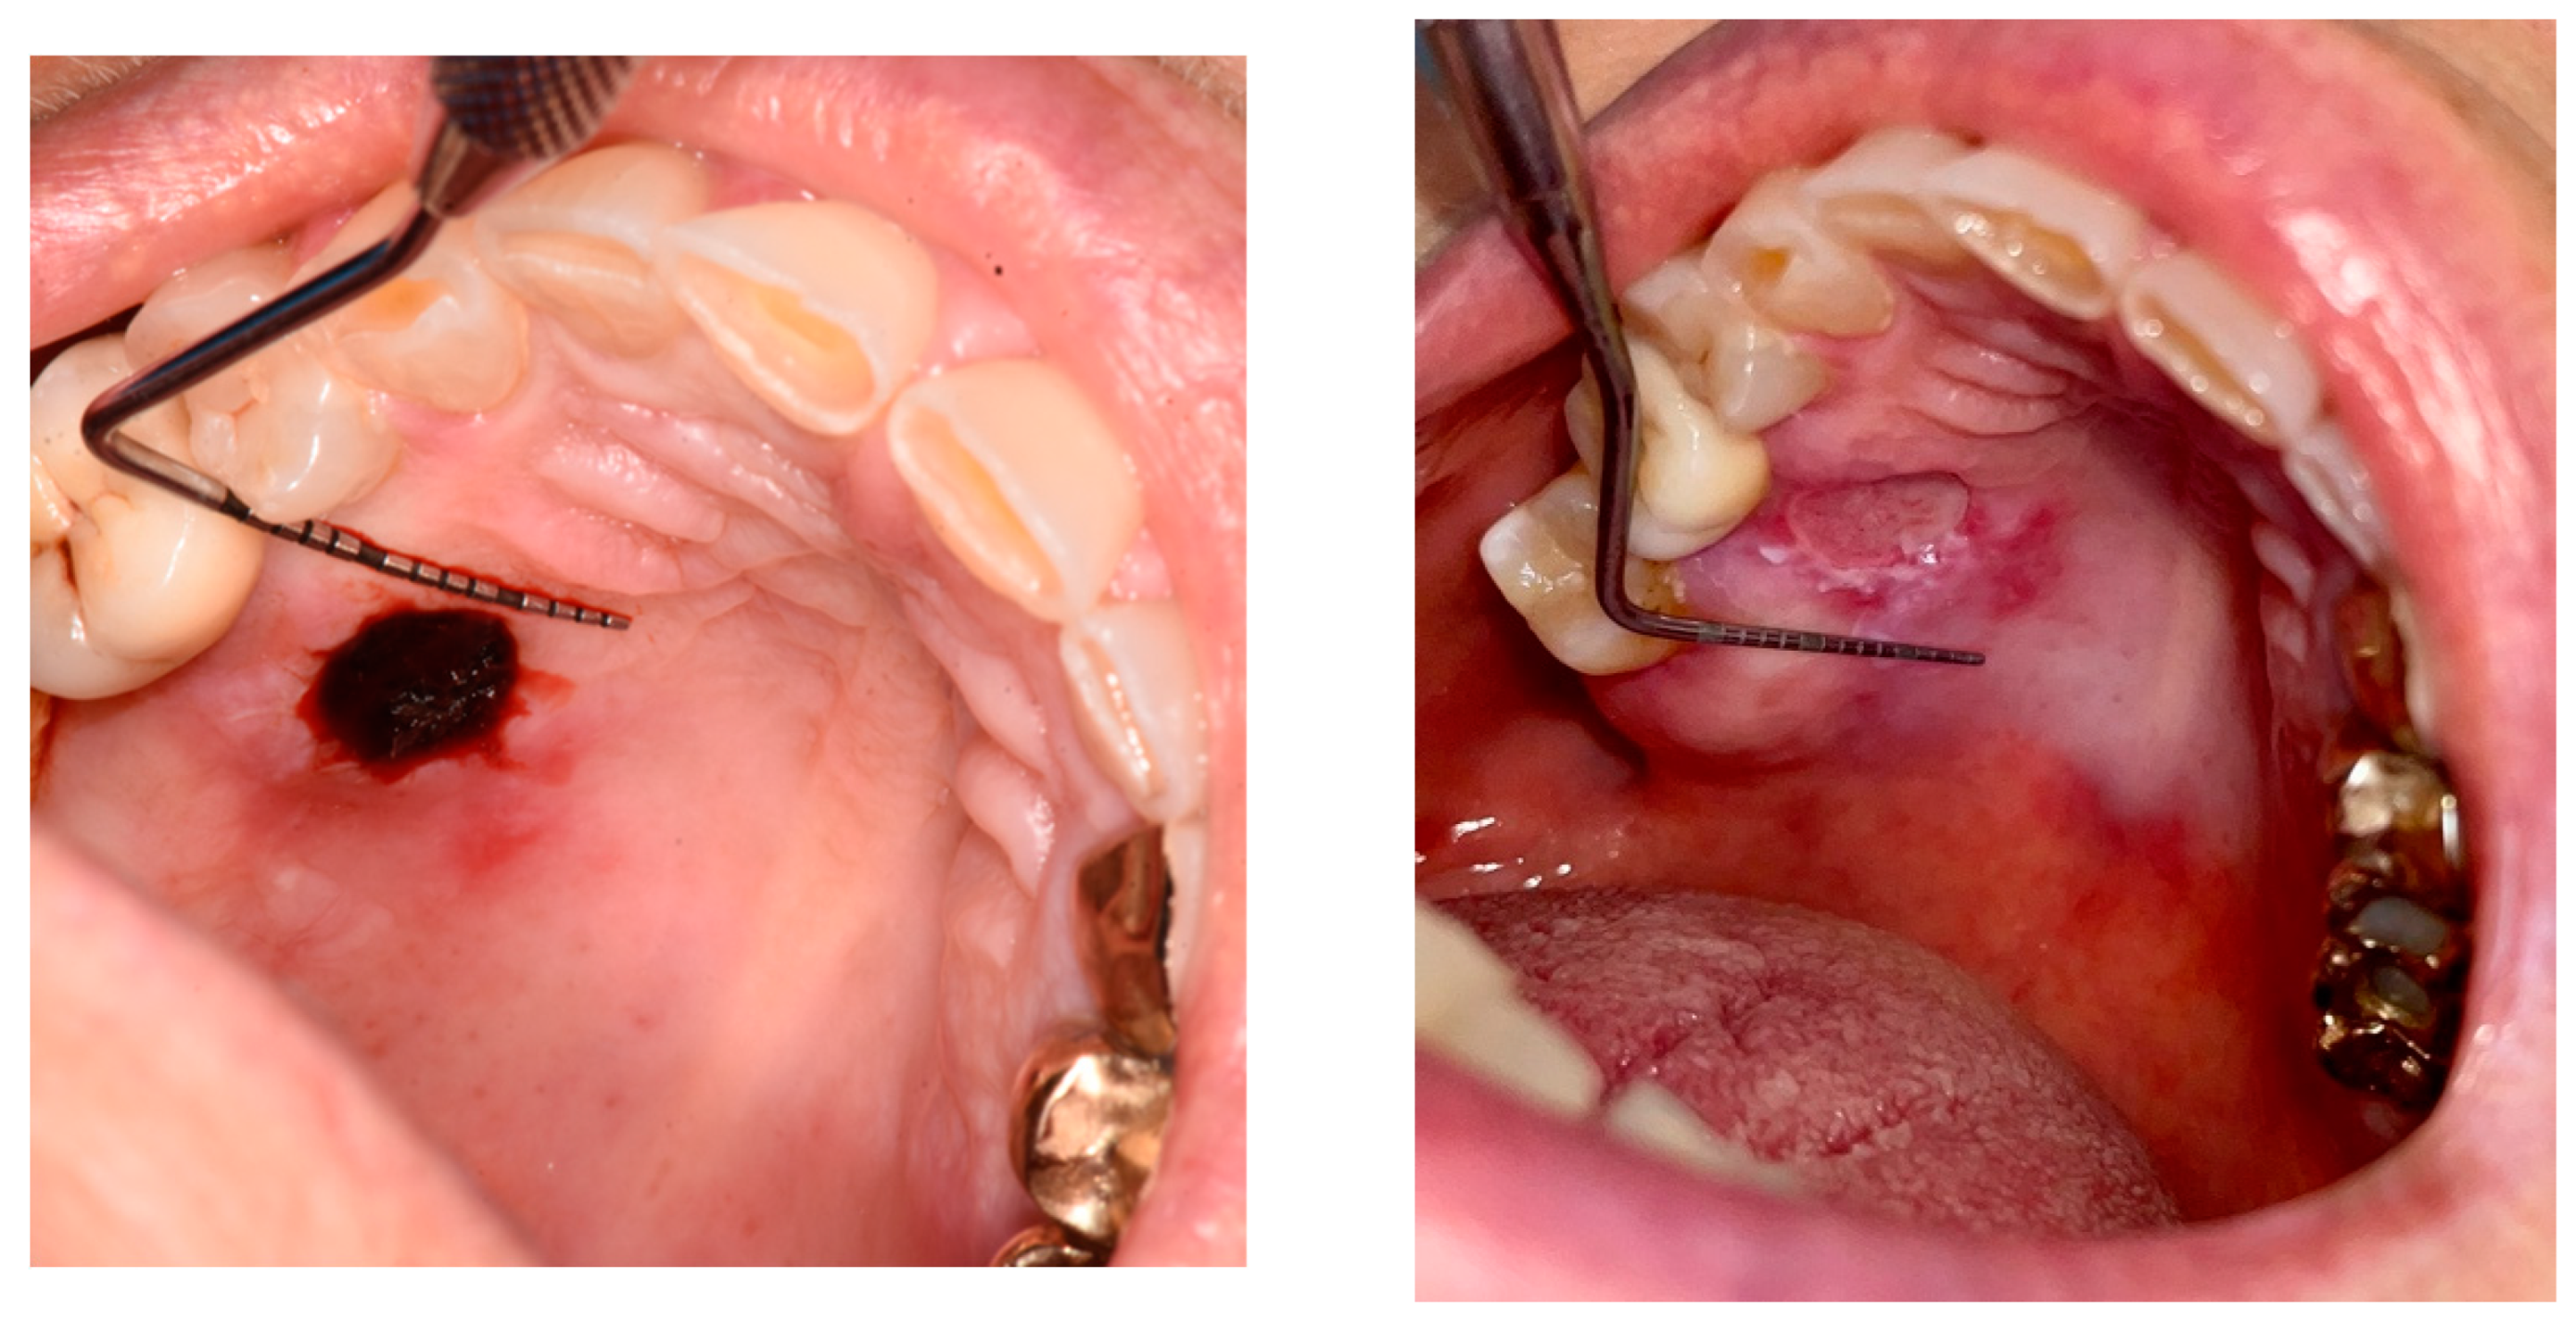

3.2. Quality of Wound Healing